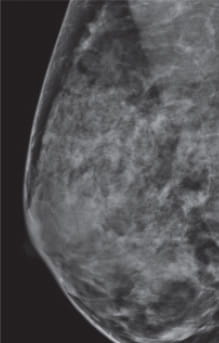

Radiologists classify breast density using a four-level density scale, as determined by a mammogram:

- Category A: Almost entirely fatty

- Category B: Scattered areas of dense breast tissue

- Category C: Heterogeneously dense

- Category D: Extremely dense

Having dense breast tissue may increase your chance of getting breast cancer. Dense breasts also make it more difficult for doctors to spot cancer on mammograms. Dense tissue appears white on a mammogram; lumps, both benign and cancerous, also appear white. So mammograms can be less accurate in women with dense breast tissue.